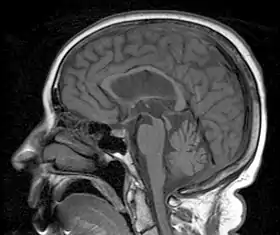

| A person with progressive dementia, ataxia, and incontinence. A clinical diagnosis of normal-pressure hydrocephalus was entertained. Imaging did not support this, however, and on formal testing, abnormal nystagmus and eye movements were detected. A sagittal view of the CT/MRI scan shows atrophy of the midbrain, with preservation of the volume of the pons. This appearance has been called the "hummingbird sign" or "penguin sign". Also, atrophy of the tectum is seen, particularly the superior colliculi. These findings suggest the diagnosis of progressive supranuclear palsy.[1] | |

Magnetic resonance imaging (MRI) is often used to diagnose PSP. MRI may show atrophy in the midbrain with preservation of the pons giving a "hummingbird" sign.[27]